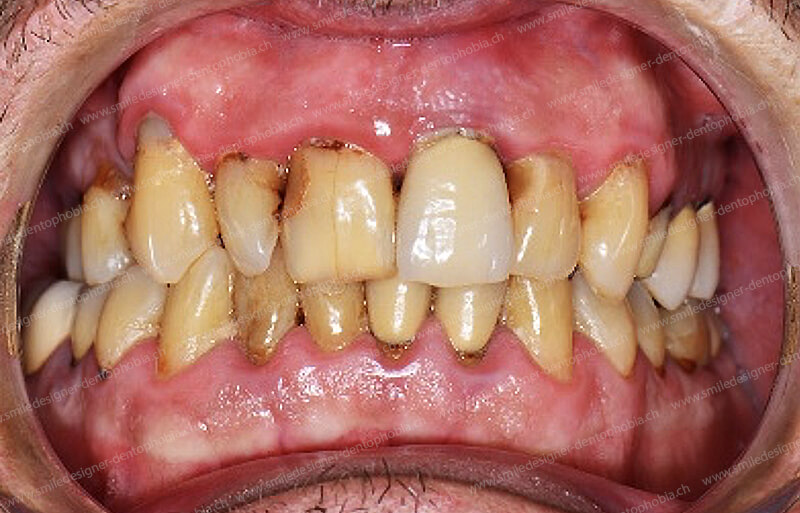

Cas clinique « GOLD STANDARD MCI » bi-maxillaire : Bridge implanto-porté sans extension (ALL ON 8) au maxillaire et à la mandibule. Version définitive des bridges avec un cosmétique en céramique.